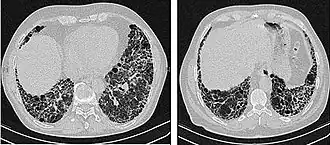

The radiological evaluation through HRCT is an essential point in the diagnostic pathway in IPF. HRCT is performed using a conventional computed axial tomographic scanner without injection of contrast agents. Evaluation slices are very thin, 1–2 mm (0.039–0.079 in).

Typical HRCT of the chest of IPF demonstrates fibrotic changes in both lungs, with a predilection for the bases and the periphery. According to the joint ATS/ERS/JRS/ALAT 2011 guidelines, HRCT is an essential component of the diagnostic pathway in IPF which can identify UIP by the presence of:[3]

- Reticular opacities, often associated with traction bronchiectasis

- Honeycombing manifested as cluster cystic airspaces, typically of comparable diameters (3–10 mm (0.12–0.39 in)) but occasionally large. Usually sub-pleural and characterized by well-defined walls and disposed in at least two lines. Generally one line of cysts is not sufficient to define honeycombing

- Ground-glass opacities are common but less extensive than the reticulation

- Distribution characteristically basal and peripheral though often patchy.